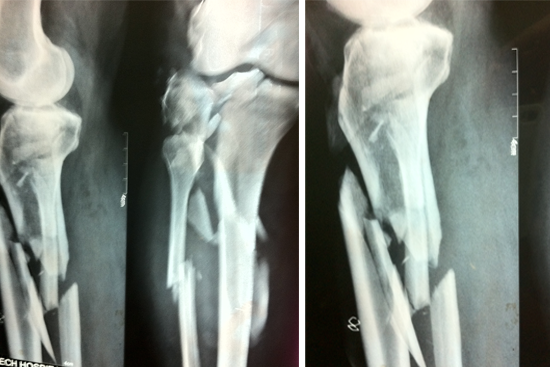

Tibialisation Of Fibula